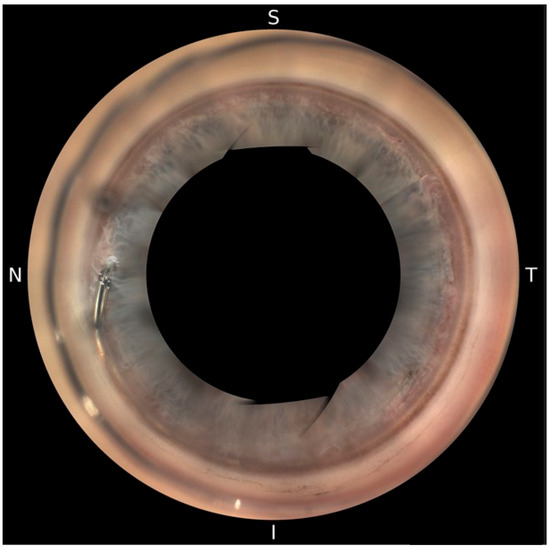

Postoperatively, patients underwent automated 360° gonioscopy to visualize the postoperative positioning of the Hydrus® Microstent (Figure 2, Figure 3 and Figure 4). The examination was performed by two experienced glaucoma specialists. Immediately after the examination, they reviewed the individual images from the 16 image directions. In addition to the individual images, 360° images of the chamber angle were obtained. Implant position was independently assessed by three experienced glaucoma specialists using the single images and the 360° composites. The postoperative position of the implant was described according to the following staging: 1a describes a protrusion of the proximal inlet into the anterior chamber. The proximal inlet (Figure 3, 1a) of the implant continues uninterrupted into a first recess, referred to here as the “first window”. This was followed by three more apertures (windows 2–4). Stage 1b describes a protrusion of the proximal end of the implant up to half the length of the first window into the anterior chamber. In Stage 1c, the entire first window is in the anterior chamber, and in Stage 1d, half of the connection (“spine”) between the first and second windows is also in the anterior chamber.

Analysis of the postoperative 360° gonoscopic images revealed the following findings: Interobserver variability in image interpretation and classification did not differ, as the structures defined for grading were clearly definable, except for the definition of distal dislocation. The final grading of the postoperative positions was in full agreement among all three subviewers. The distribution of the different implant positions is shown in Table 3. Figure 3 shows the different types of positions of the proximal and distal tip. In four implants only, the inlet was in the anterior chamber (1a). In 14 cases, approximately half of the first window of the stent (viewed from the proximal end with the inlet in the anterior chamber) protruded into the anterior chamber (1b). In three cases, the entire first window was in the anterior chamber (1c). In two cases, at least half of the bridge, called the spine, was visible between the first and second windows in the anterior chamber (1d). In no case was the second window (viewed from the proximal end with the entrance in the anterior chamber) visible in the anterior chamber.

Figure 2. Hydrus® Microstent visualized with NIDEK GS-1 Gonioscope.

Figure 3. Visualization of the postoperative position of the proximal and distal tips of the Hydrus® Microstent using automated 360° gonioscopy. Only the proximal tip is visible in the anterior chamber (1a). Half of the first window of the stent (viewed from the proximal end with the inlet in the anterior chamber) protrudes into the anterior chamber (1b). The entire first window is in the anterior chamber (1c). At least half of the bridge, called the spine, between the first and second windows is in the anterior chamber (1d). The distal rounded tip is clearly visible behind the trabecular meshwork within Schlemm’s canal (2a). The distal tip protrudes into the anterior chamber (2b). The distal stent is not visible through the trabecular meshwork, suggesting a posterior location (2c).